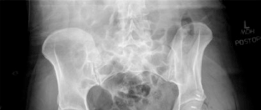

Radiographic and Advanced Imaging

Standard preoperative imaging must include an anteroposterior (AP) pelvis, cross-table lateral, and false-profile view of the affected hip. These evaluate for dysplasia, impingement morphology (cam/pincer), and degenerative changes.

Magnetic Resonance Arthrography (MRA) is the gold standard for evaluating the capsuloligamentous complex. Extravasation of contrast anteriorly often delineates the size and location of the capsular defect. MRA also assesses labral integrity, chondral damage, and the viability of the femoral head. A 3D computed tomography (CT) scan is highly recommended to quantify femoral anteversion and acetabular version, as unrecognized osseous malorientation (e.g., severe femoral retroversion) will predispose the reconstruction to failure if not addressed concurrently with a derotational osteotomy.